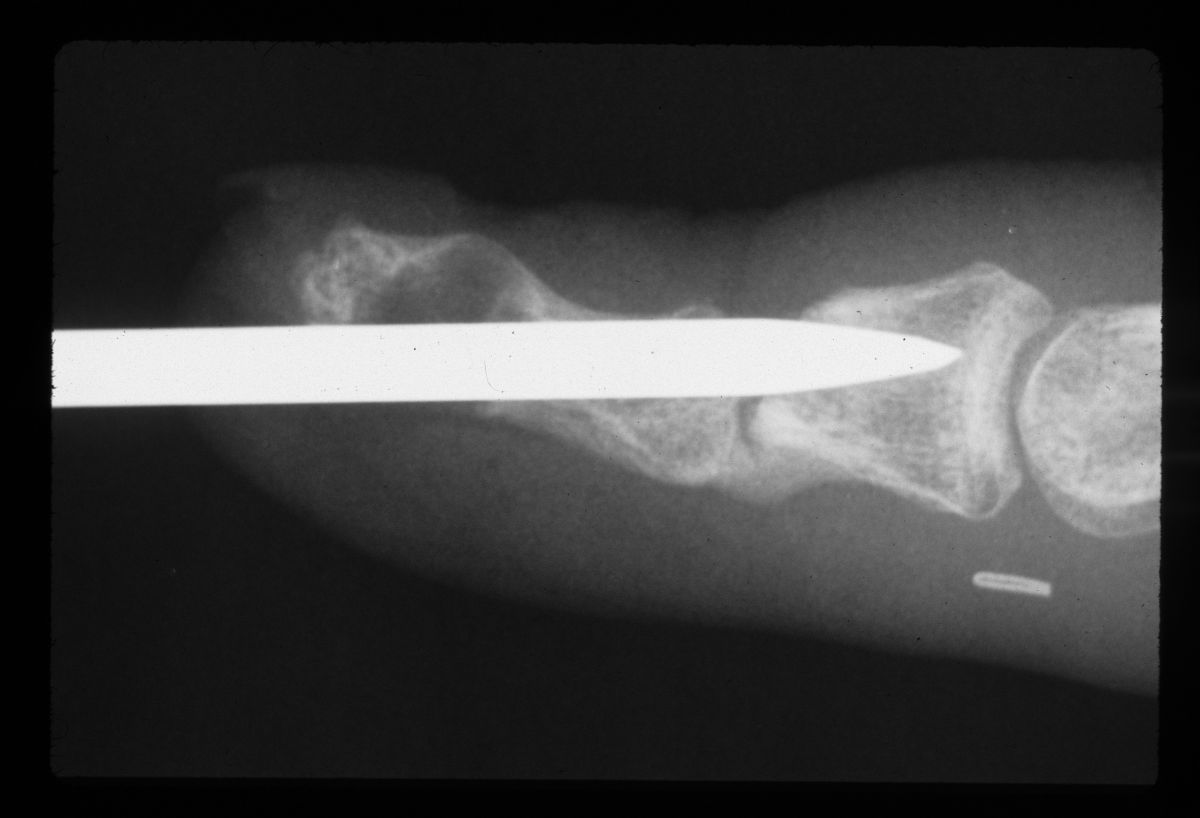

| The graft was sculpted to the diameter of a Steinmann pin. |

| That pin was used as a drill and then replaced with the bone graft. The cyst defect was packed with cancellous bone. |

| Temporary pin placement. |

| After tapping the bone graft into place. |